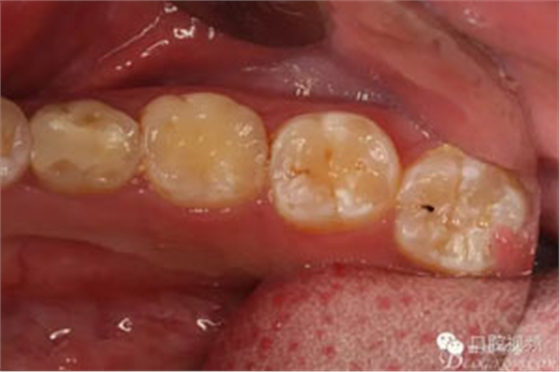

圖3.術(shù)前口內(nèi)照片,舌側(cè)外形無(wú)隆起。光滑平整。